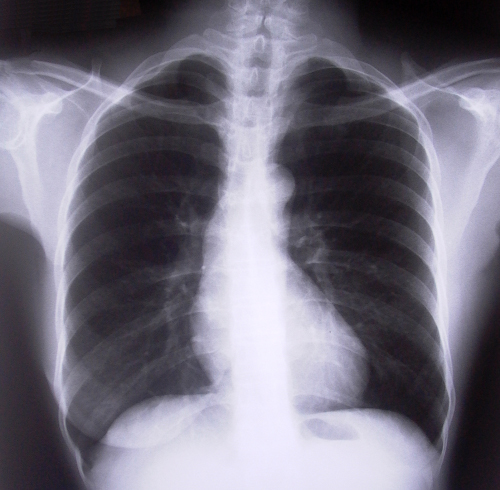

I pazienti affetti da tumore sottoposti a chemioterapia hanno maggiori probabilità di sviluppare coaguli di sangue. Oltre a costituire un rischio significativo per problemi al cuore, al cervello ed ai polmoni, i coaguli di sangue sono particolarmente difficili da trattare nei malati di cancro e molte volte possono indurre i medici a sospendere la chemioterapia, o accompagnare questa con terapie di profilassi per evitare il rischio di tromboembolia, che tra l’altro fanno aumentare notevolmente i costi già elevati cui devono far fronte i pazienti.